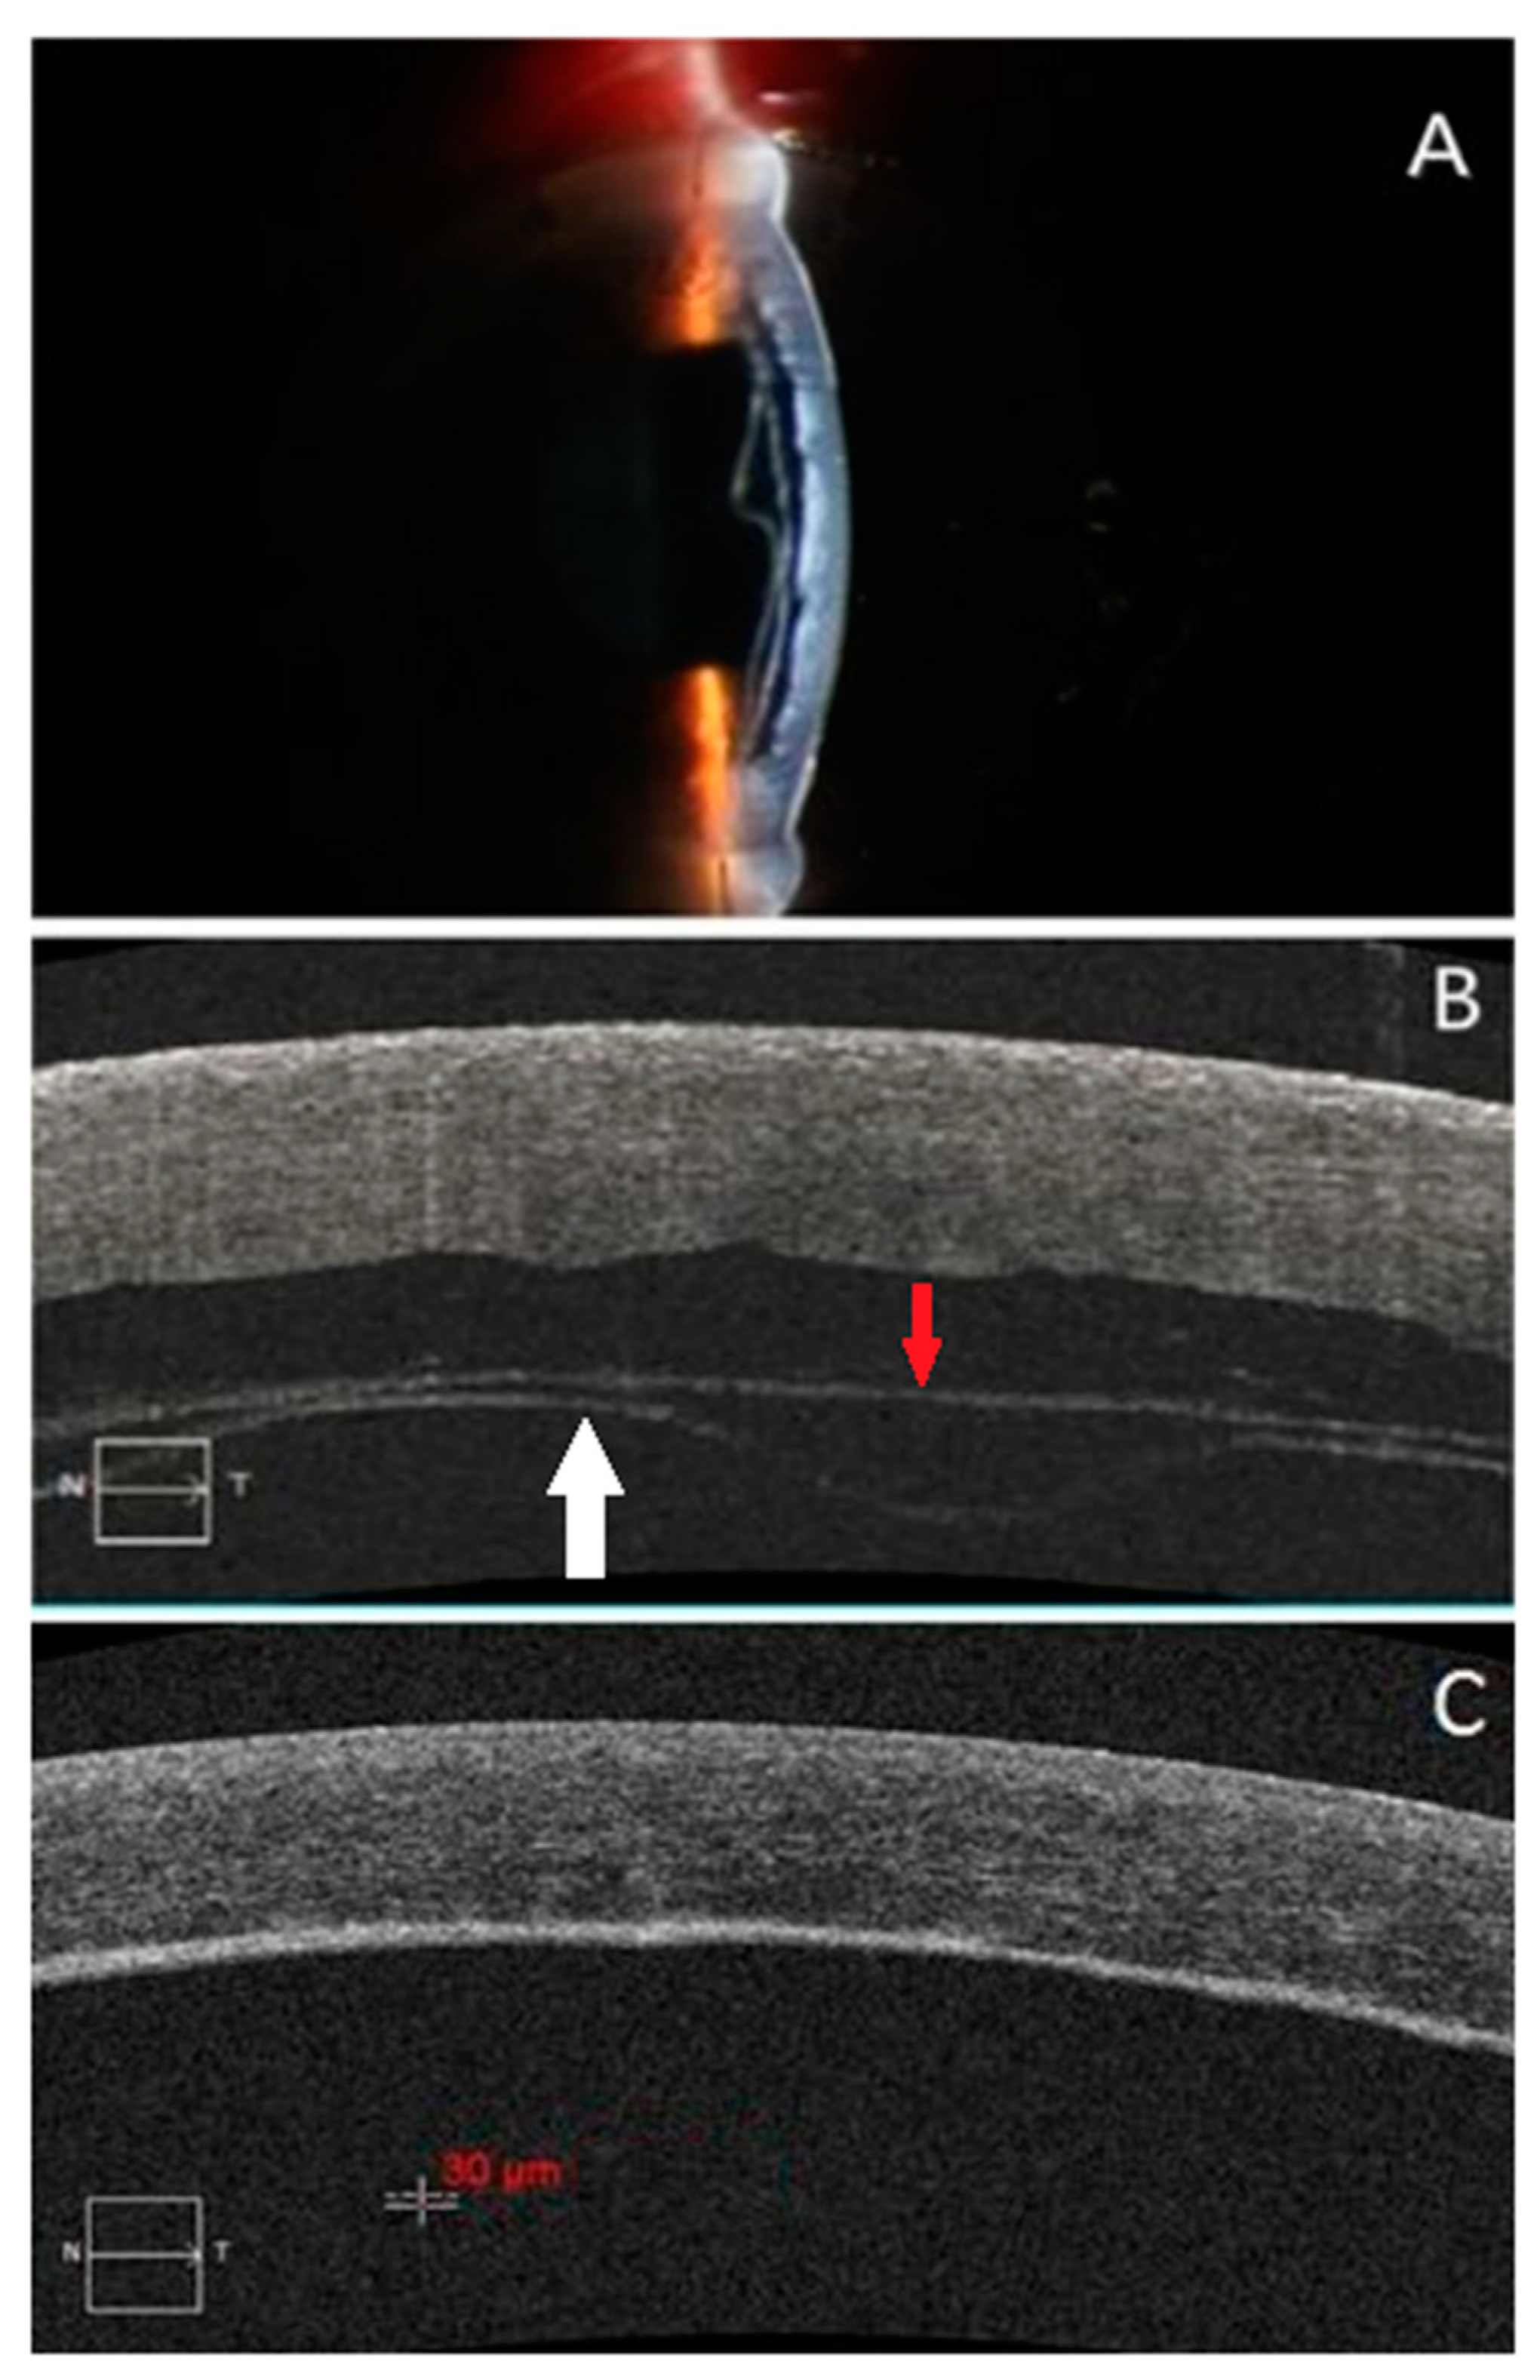

2. Subjects

3. Image Acquisition and Processing